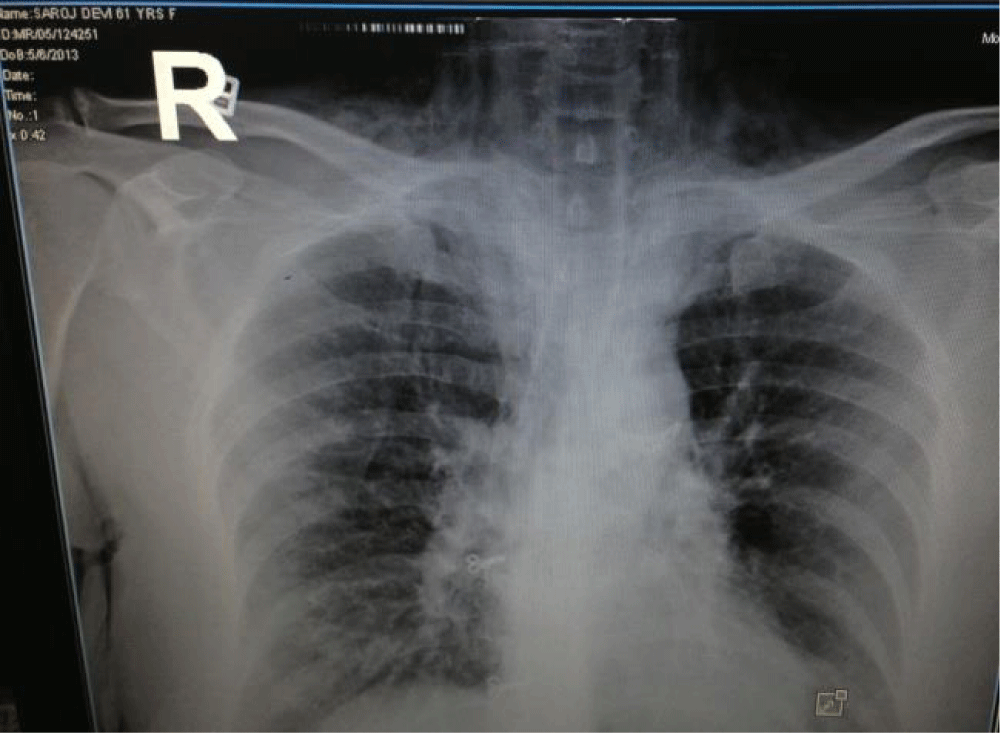

On day two, a swelling was noticed in the lower neck with crepitus on palpation suggestive of subcutaneous emphysema (Figure 2). She also complained of breathing difficulty. An urgent chest x ray was done (Figure 3) which revealed subcutaneous emphysema over lower neck, pneumomediastenum with clear lung fields without pneumothorax. Contrast Enhanced CT Scan (CECT) of thorax showed air density around trachea suggestive of pneumomediastinum (Figure 4). Lung parenchyma showed interstitial fibrosis with honey combing in basal segments of lower zones bilaterally. Her Creatine Kinase-MB values of blood samples taken 6 hours apart were within normal limits and echocardiography did not show Regional Wall Motion (RWMA) abnormality.

Her treatment for ACS was immediately stopped. She was managed with supplemental high flow oxygen and analgesics. Her immunosuppressive therapy was continued. She made an uneventful recovery and was discharged after 10 days and is doing well at follow up. Her chest radiograph done 10 days later showed resolution of the pneumomediastenum with resolution of ECG changes to normal (Figure 5). Coronary Angiography (CAG) done subsequently was normal.